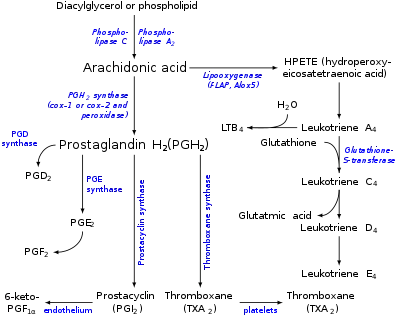

Biosynthesis Eicosanoids

Two families of enzymes catalyze fatty acid oxygenation to produce the eicosanoids:

- Cyclooxygenase, or COX, generates the prostanoids.

- Lipoxygenase, or LOX, in several forms. 5-lipoxygenase (5-LO) generates the leukotrienes.

Eicosanoids are not stored within cells, but are synthesized as required. They derive from the fatty acids that make up the cell membrane and nuclear membrane.

Eicosanoid biosynthesis begins when cell is activated by mechanical trauma, cytokines, growth factors or other stimuli. (The stimulus may even be an eicosanoid from a neighboring cell; the pathways are complex.) This triggers the release of a phospholipase at the cell membrane. The phospholipase travels to the nuclear membrane. There, the phospholipase catalyzes ester hydrolysis of phospholipid (by A2) or diacylglycerol (by phospholipase C). This frees a 20-carbon essential fatty acid. This hydrolysis appears to be the rate-determining step for eicosanoid formation.

The fatty acids may be released by any of several phospholipases. Of these, type IV cytosolic phospholipase A2 (cPLA2) is the key actor, as cells lacking cPLA2 are generally devoid of eicosanoid synthesis. The phospholipase cPLA2 is specific for phospholipids that contain AA, EPA or GPLA at the SN2 position. Interestingly, cPLA2 may also release the lysophospholipid that becomes platelet-activating factor.[7]

Next, the free fatty acid is oxygenated along any of several pathways; see the Pathways table. The eicosanoid pathways (via lipoxygenase or COX) add molecular oxygen (O2). Although the fatty acid is symmetric, the resulting eicosanoids are chiral; the oxidation proceeds with high stereospecificity.

Biosynthesis of Prostanoid

Cyclooxygenase (COX) catalyzes the conversion of the free essential fatty acids to prostanoids by a two-step process. In the first step, two molecules of O2 are added as two peroxide linkages and a 5-member carbon ring is forged near the middle of the fatty acid chain. This forms the short-lived, unstable intermediate Prostaglandin G (PGG). One of the peroxide linkages sheds a single oxygen, forming PGH. (See diagrams and more detail at Cyclooxygenase). All other prostanoids originate from PGH (as PGH1, PGH2, or PGH3).

Figure 1 shows how PGH2 (derived from Arachidonic acid) is converted:

- By PGE synthetase into PGE (which in turn is converted into PGF)

- By PGD synthetase into PGD

- By Prostacyclin synthase into prostacyclin (PGI2)

- By Thromboxane synthase into thromboxanes

The three classes of prostanoids have distinctive rings in the center of the molecule. They differ in their structures. The PGH compounds (parents to all the rest) have a 5-carbon ring, bridged by two oxygens (a peroxide.) The derived prostaglandins contain a single, unsaturated 5-carbon ring. In prostacyclins, this ring is conjoined to another oxygen-containing ring. In thromboxanes the ring becomes a 6-member ring with one oxygen.

Leukotrienes pathway

Leukotrienes are synthesized in the cell from arachidonic acid by 5-lipoxygenase. The catalytic mechanism involves the insertion of an oxygen moiety at a specific position in the arachidonic acid backbone. The lipoxygenase pathway is active in leukocytes, including mast cells, eosinophils, neutrophils, monocytes, and basophils. When such cells are activated, arachidonic acid is liberated from cell membrane phospholipids by phospholipase A2, and donated by the 5-lipoxygenase-activating protein (FLAP) to 5-lipoxygenase. 5-Lipoxygenase (5-LO) uses FLAP to convert arachidonic acid into 5-hydroperoxyeicosatetraenoic acid (5-HPETE), which spontaneously reduces to 5-hydroxyeicosatetraenoic acid (5-HETE). The enzyme 5-LO acts again on 5-HETE to convert it into leukotriene A4 (LTA4), an unstable epoxide. In cells equipped with LTA4 hydrolase, such as neutrophils and monocytes, LTA4 is converted to the dihydroxy acid leukotriene LTB4, which is a powerful chemoattractant for neutrophils acting at BLT1 and BLT2 receptors on the plasma membrane of these cells. In cells that express LTC4 synthase, such as mast cells and eosinophils, LTA4 is conjugated with the tripeptide glutathione to form the first of the cysteinyl-leukotrienes, LTC4. Outside the cell, LTC4 can be converted by ubiquitous enzymes to form successively LTD4 and LTE4, which retain biological activity. The cysteinyl-leukotrienes act at their cell-surface receptors CysLT1 and CysLT2 on target cells to contract bronchial and vascular smooth muscle, to increase permeability of small blood vessels, to enhance secretion of mucus in the airway and gut, and to recruit leukocytes to sites of inflammation. Both LTB4 and the cysteinyl-leukotrienes (LTC4, LTD4, LTE4) are partly degraded in local tissues, and ultimately become inactive metabolites in the liver.

Cyclooxygenase (COX)

COX converts arachidonic acid (AA, an ω-6 PUFA) to prostaglandin H2 (PGH2), the precursor of the series-2 prostanoids. The enzyme contains two active sites: a heme with peroxidase activity, responsible for the reduction of PGG2 to PGH2, and a cyclooxygenase site, where arachidonic acid is converted into the hydroperoxy endoperoxide prostaglandin G2 (PGG2). The reaction proceeds through H atom abstraction from arachidonic acid by a tyrosine radical generated by the peroxidase active site. Two O2 molecules then react with the arachidonic acid radical, yielding PGG2. At present, three COX isoenzymes are known: COX-1, COX-2, and COX-3. COX-3 is a splice variant of COX-1, which retains intron one and has a frameshift mutation; thus some prefer the name COX-1b or COX-1 variant (COX-1v).[3] Different tissues express varying levels of COX-1 and COX-2. Although both enzymes act basically in the same fashion, selective inhibition can make a difference in terms of side-effects. COX-1 is considered a constitutive enzyme, being found in most mammalian cells. COX-2, on the other hand, is undetectable in most normal tissues. It is an inducible enzyme, becoming abundant in activated macrophages and other cells at sites of inflammation. More recently, it has been shown to be upregulated in various carcinomas and to have a central role in tumorigenesis. Both COX-1 and -2 (also known as PGHS-1 and -2) also oxygenate two other essential fatty acids – DGLA (ω-6) and EPA (ω-3) – to give the series-1 and series-3 prostanoids, which are less inflammatory than those of series-2. DGLA and EPA are competitive inhibitors with AA for the COX pathways. This inhibition is a major mode of action in the way that dietary sources of DGLA and EPA (e.g., borage, fish oil) reduce inflammation.The use of anabolic steroids is now banned by all major sporting bodies, including the ATP, WTA, ITF, International Olympic Committee, FIFA, UEFA, all major professional golf tours, the National Hockey League, Major League Baseball, the National Basketball Association, the European Athletic Association, WWE and the NFL. However drug testing can be wildly inconsistent and, in some instances, has gone unenforced.